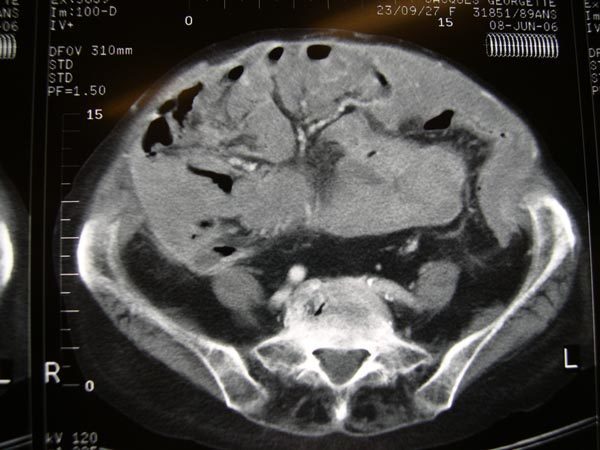

Quel est votre diagnostic ?

Il s'agit bien d'un mésothéliome péritonéal.